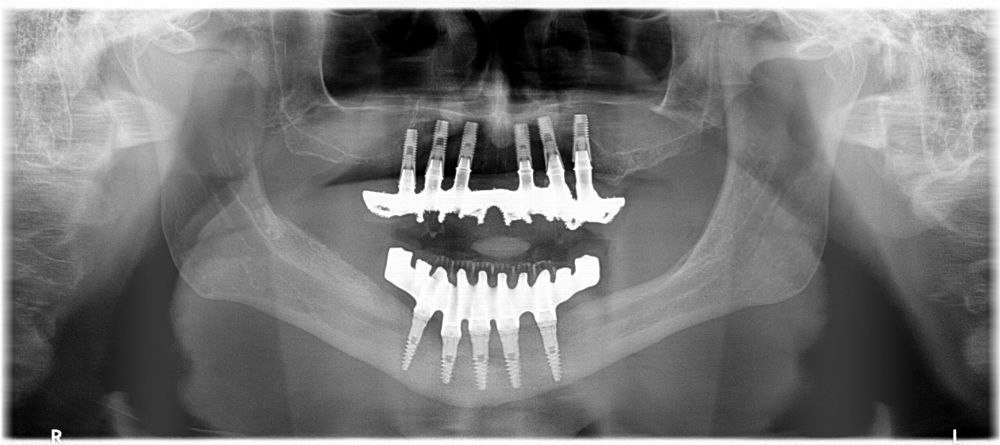

Clinical Case: A subperiosteal sintered titanium structure was fabricated with six transepithelial connections that were rehabilitated with an immediate implant supported fixed prosthesis made of PMMA. Two months later, a sintered chromium-cobalt framework with machined bases covered with acrylic resin teeth was fabricated as the final restoration. At one year follow-up, the case remains stable.

Subperiosteal implants (SI) were developed in Sweden in the early 1940´s. The SI consisted of a custom-made implant, inserted under the periosteum and fixed with screws and the mucous tissue that covered it3,4. They were manufactured in chromium-cobalt or titanium alloys and were rehabilitated by transmucous pillars that emerged in the oral cavity5. Although they were used for years in cases of maxilla atrophies, they were replaced by endoosseous implants designed by Branemark6. This was due to its complex manufacturing. It was necessary to take an impression of the residual bone ridge, which was sent to the laboratory for the structure design, with the consequent imbalances since they were not very stable models. In this way, its placement in the patient was very difficult, and several complications could appear7,8. However, advances in the planning and manufacturing field with various materials have allowed these structures to be made digitally with an excellent predictability and fit, thus avoiding more complex surgeries9.